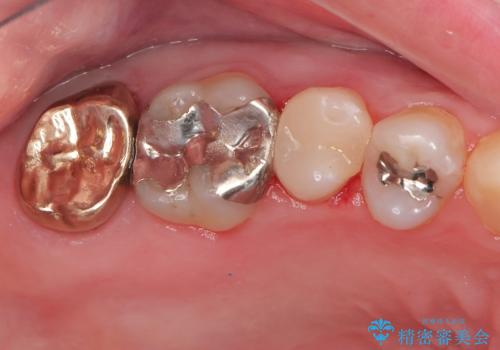

- 他院で右奥歯の治療が必要と言われて来院。

レントゲンと,CT撮影を行なったところ右上小臼歯が虫歯、右上第二大臼歯には根の先に大きな病気がありました。

手前の歯はセラミック治療を行い、奥の歯は精密根管治療を行いゴールドクラウンで治療を行いました。

セラミックインレーは古い材料を拡大鏡でしっかり取り除き適合の良い詰め物が装着されました。

根管治療はラバーダム防湿を行い、無菌的な状態で治療を行っています。

CTでは経過良好で経過観察を行なっていきます。